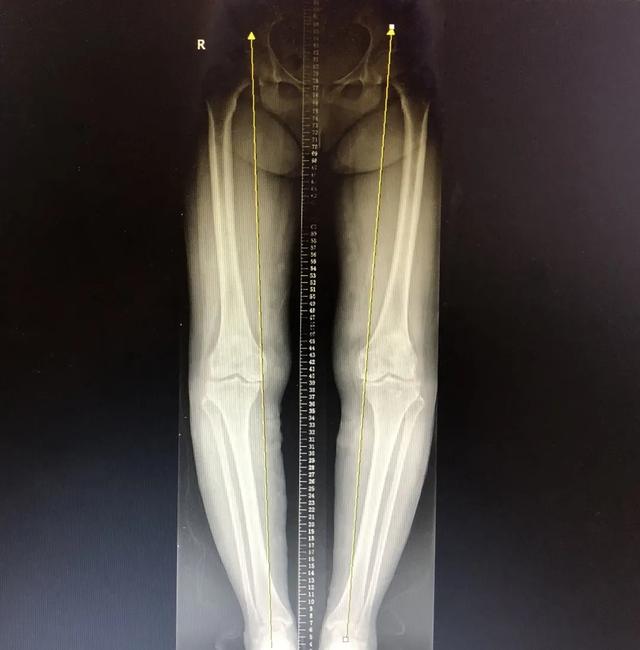

经朋友介绍,冯阿姨来到了重庆北部宽仁医院,骨科周平主治医师为冯阿姨接诊。经过仔细的查体、阅片,结合冯阿姨的临床症状:关节间隙狭窄、膝关节内翻,证实了冯阿姨患「双膝重度骨关节炎并内翻曲屈畸形」,临床症状较重,应予以 「人工全膝关节置换术」 (total knee arthroplasty,TKA)。

术前